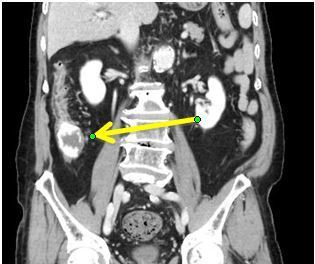

大腸憩室出血に対する緊急止血術

- CTで大腸内に造影剤の漏出がみられる(出血を表している)。